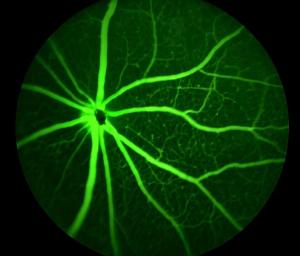

Age-Related Macular Degeneration is a chronic disease of the macula, the part at the centre of the retina which controls the eye’s ability to focus.

There are two stages of the disease. Wet AMD is characterised by the formation of blood vessels at the back of the eye. Dry AMD is a combination of the breakdown of the Bruch’s membrane, which maintains the function of photoreceptors and the death of retinal pigment epithelial (RPE) cells in the macula.

Researchers from Bond University believe they are on the cusp of reversing vision loss through stem cell therapy in which manufactured synthetic epithelial cells are transplanted into the eye, reversing the death of photoreceptors that detect light and transmit visual signals to the brain.

The team is working to develop and test a delivery system of stem cell-derived RPE cells, supported by a prosthetic membrane, that can form a uniform monolayer of pigmented cells which function like cells in the healthy eye.